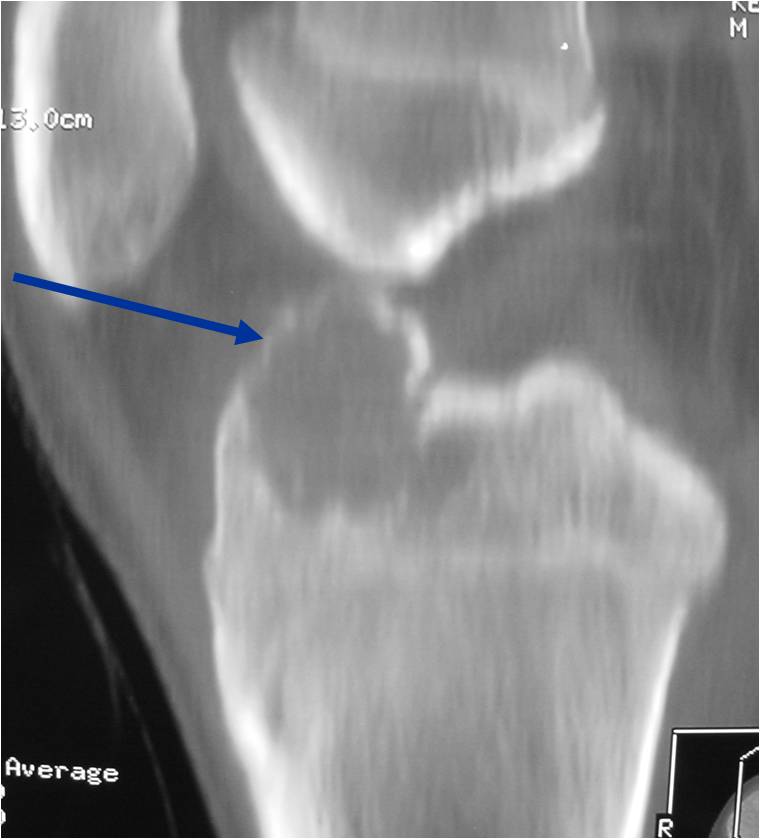

- (CT appearance)

- Most useful for detecting subtle mineralization not apparent on X-rays

- Useful for identifying intact periosteum around any expansile soft tissue component

- surrounding thin reactive shell of bone/mineralization (Egg Shell Rim of Calcification)

- helps place the tumor in a benign category

- helps evaluate:

- bony quality

- extent of bone and cortical destruction

- whether the subchondral plate of bone adjacent to the articular cartilage has been destroyed or is intact